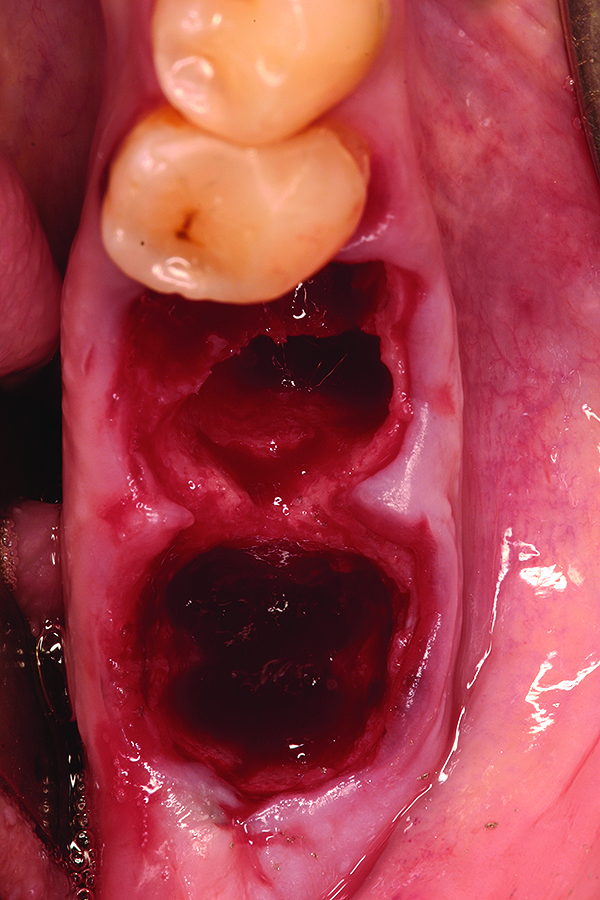

Fig 2. Atraumatic extraction of hopeless mandibular first and second molars.

Figure 2

Fig 3. Placement of bone allograft into extraction sites.

Figure 3